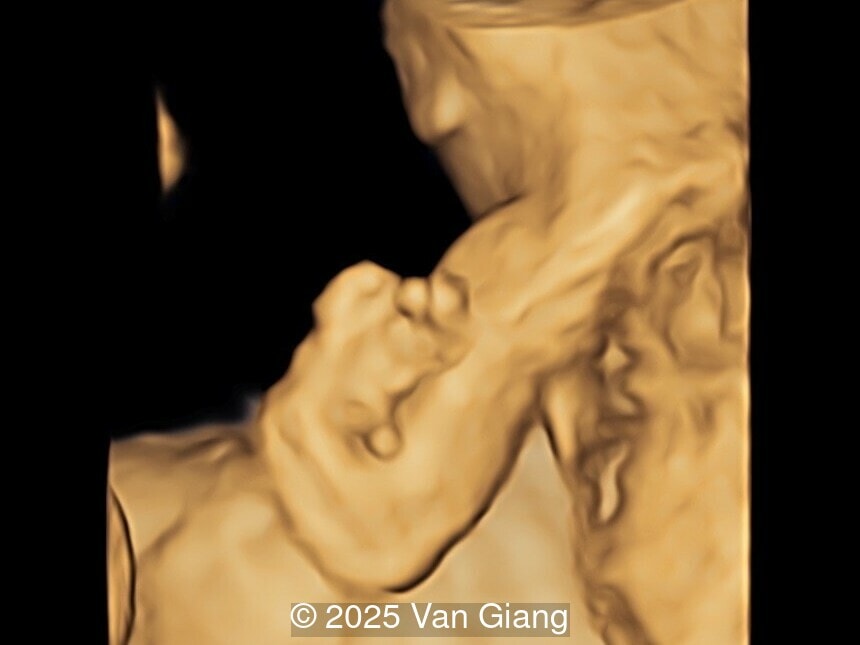

A 32-year-old primigravida presents at 20 weeks gestation without first trimester screening. Ultrasound reveals a small for gestational age fetus with the following anomalies:

Ultrasound revealed severe mandibular and zygomatic hypoplasia, glossoptosis, cleft palate, and micrognathia with an abnormal facial profile. Both upper limbs showed radial ray sequence with abnormal thumbs and shortened forearms. Unilateral clubfoot was also noted. No major cardiac or visceral anomalies were observed. Based on these findings, Nager syndrome was suspected.

Left hand

Image 4 Left hand